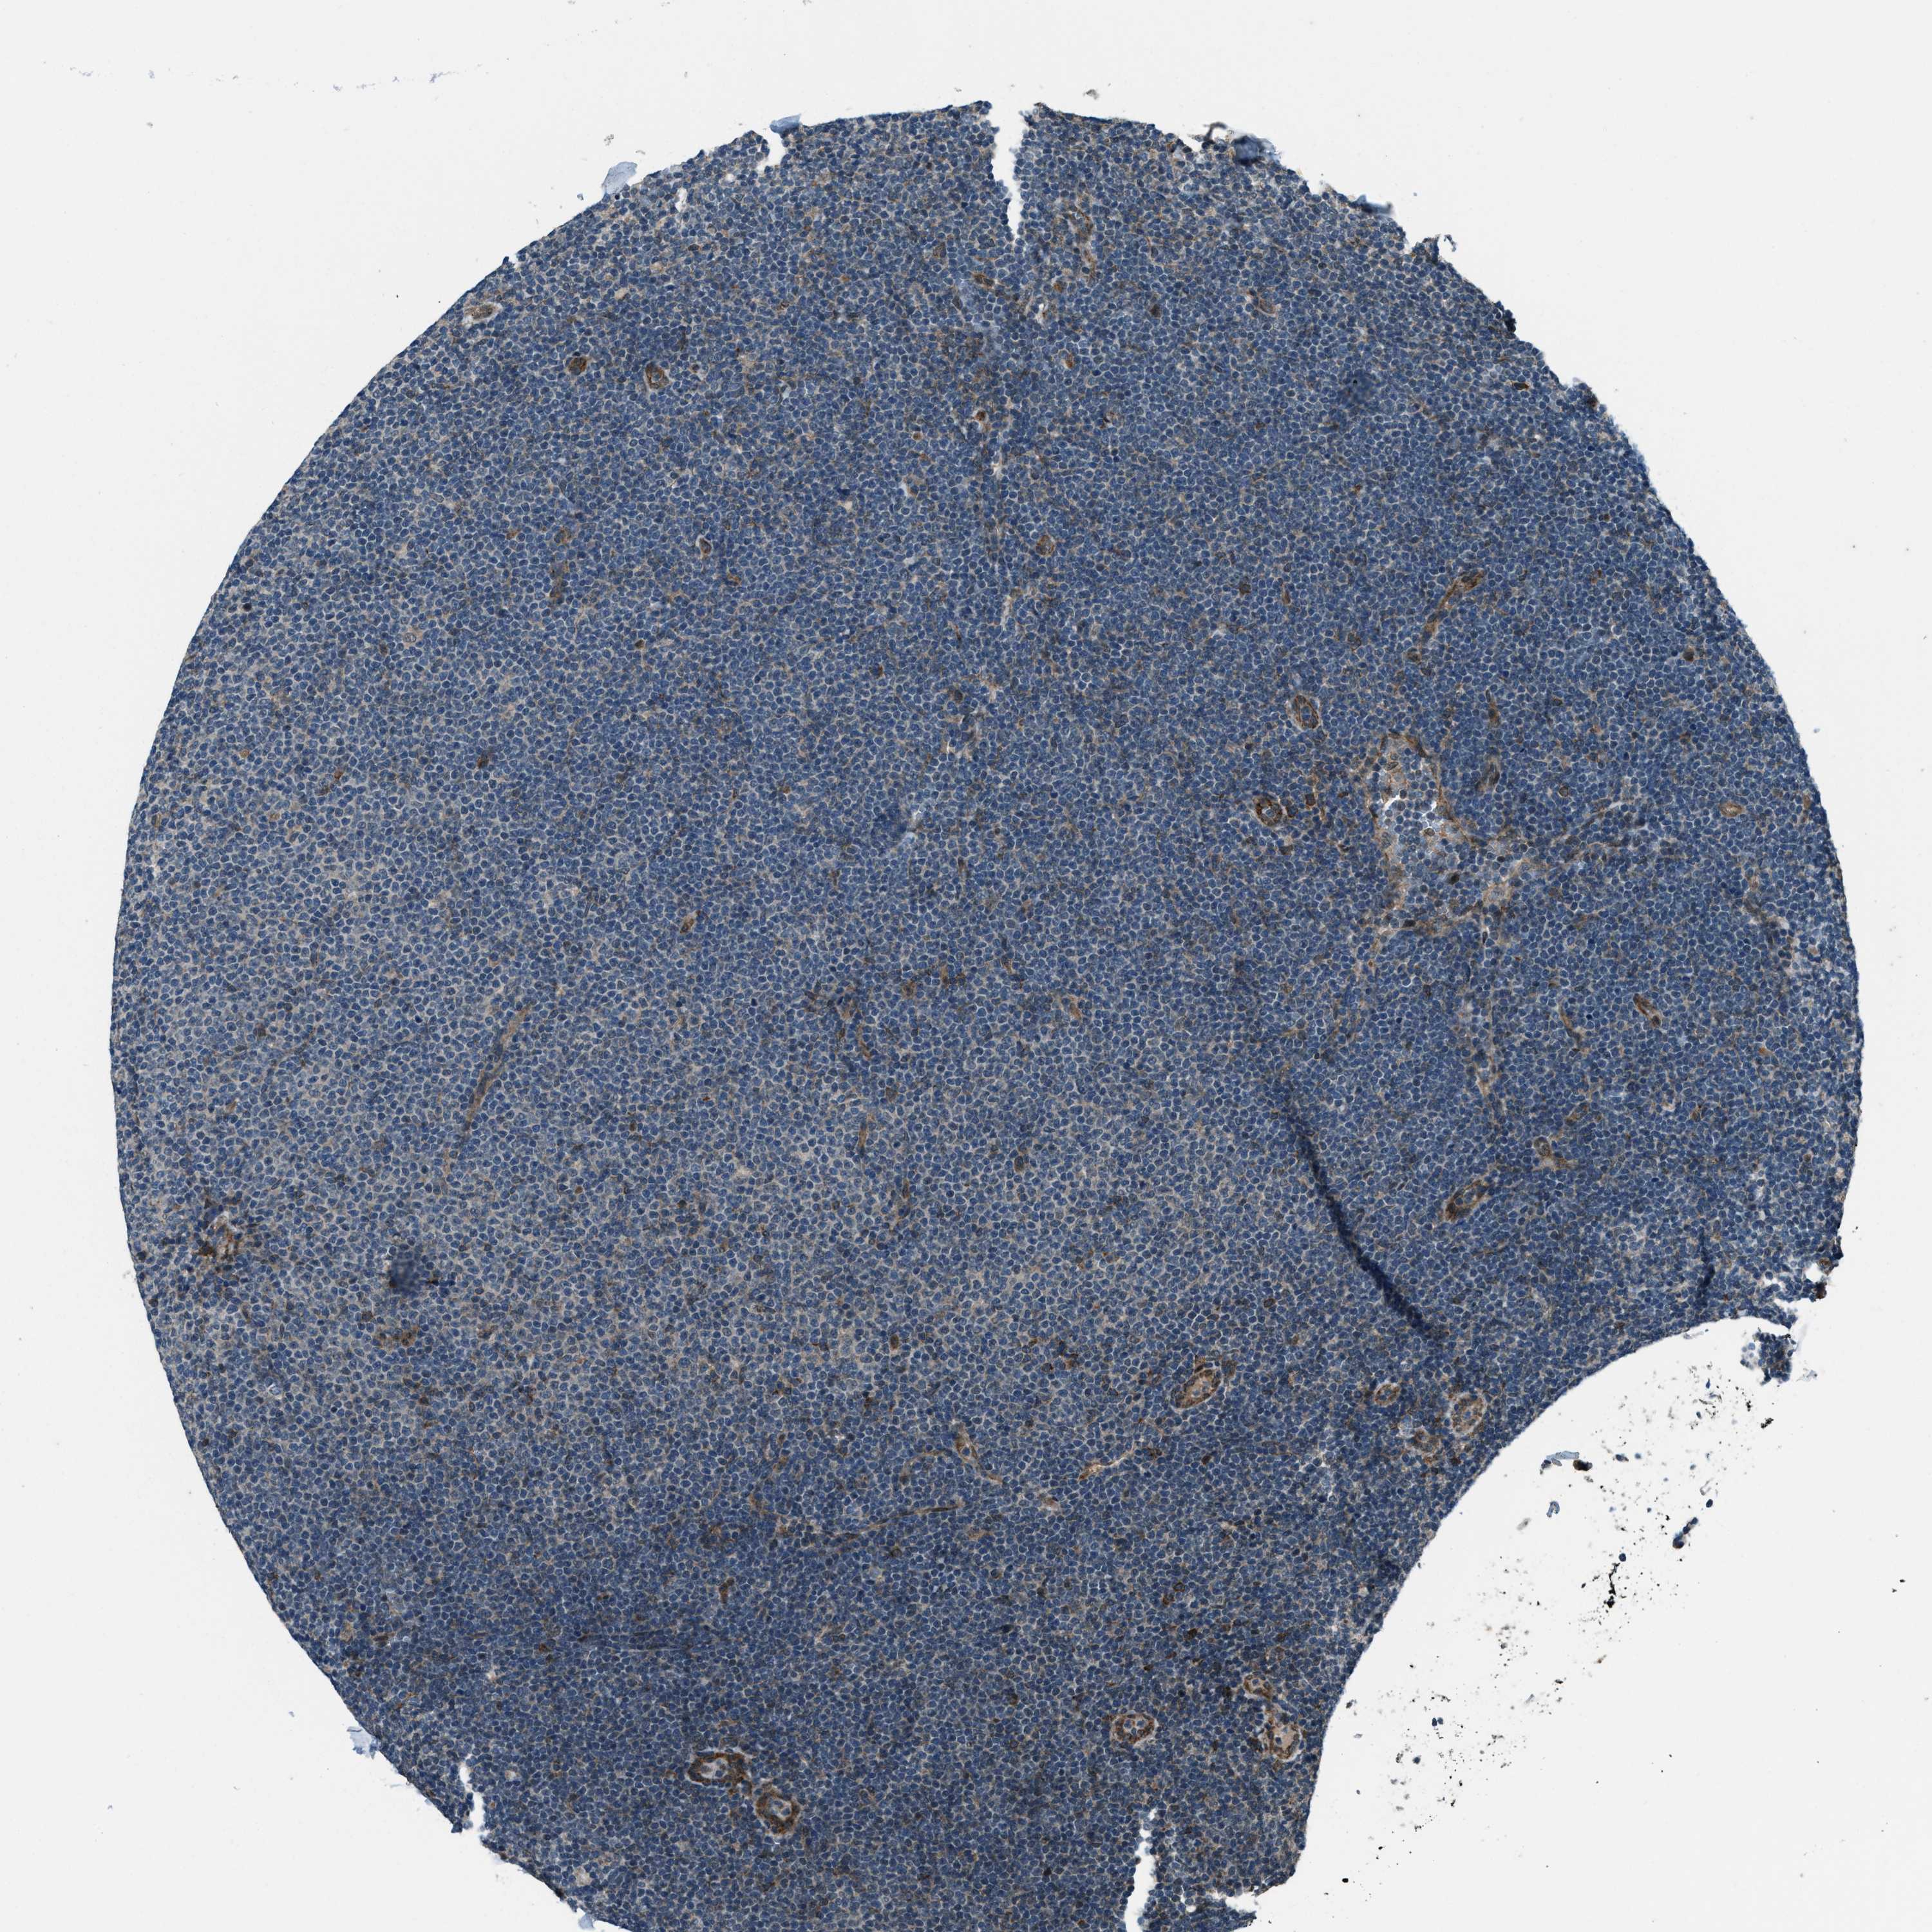

CANCER LYMPHOMA Show tissue menu

LYMPHOMA - Protein expressioni

A mouse-over function shows sample information and annotation data. Click on an image to view it in a full screen mode. Samples can be filtered based on level of antibody staining by selecting one or several of the following categories: high, medium, low and not detected. The assay and annotation is described here.

Each image is clickable and will lead to virtual microscopy that enables deeper exploration of all samples and also displays staining intensity scores, fraction scores and subcellular localization as well as patient and tissue information for each sample.

Antibody HPA020095

Antibody HPA020138

Antibody CAB010878

Antibody CAB080402

Hodgkin's disease, NOS

Malignant lymphoma, non-Hodgkin's type, High grade

Malignant lymphoma, non-Hodgkin's type, Low grade